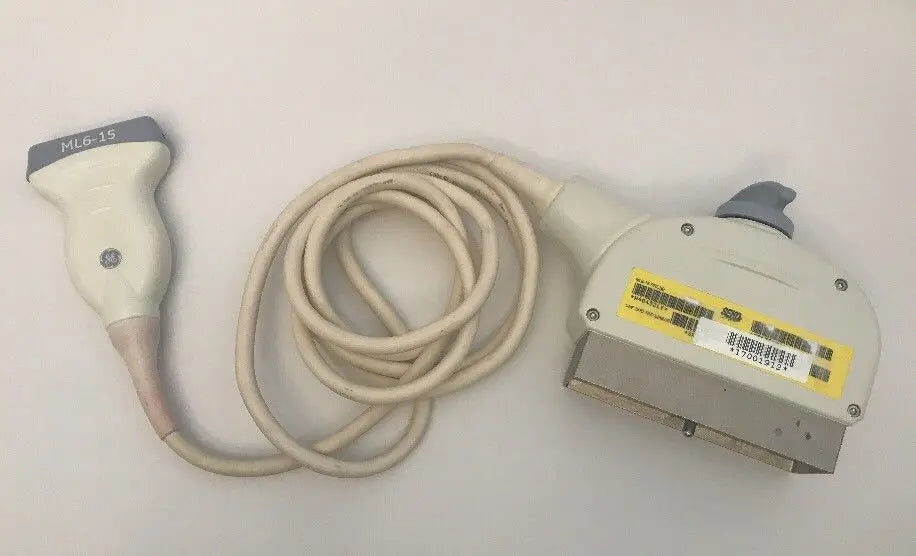

DIAGNOSTIC ULTRASOUND MACHINES FOR SALE

2017 GE ML6-15 -RS for GE S8 ,S6 Ultrasound

Sale price$ 7,675.18